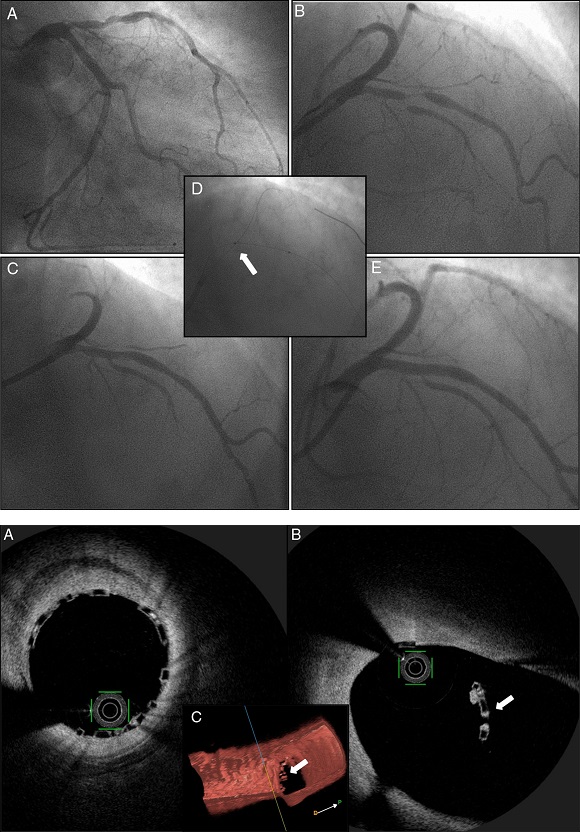

Carlos Galvão Braga, Raymundo Ocaranza-Sánchez, Santiago Gestal, Ramiro Trillo, José Ramón González-Juanatey

Conclusions: To our knowledge, this case reports for the first time the feasibility and safety of the Szabo technique in an ostial lesion with BRS implantation. The use of intracoronary OCT imaging enabled us to ensure and document an excellent result with this technique.

UP: Figure 1. Coronary angiography showing severe disease of the mid left anterior descending (LAD) artery, involving the bifurcation with the first major septal branch (Medina 1,1,1) (A and B); after angioplasty of the first septal branch with a drug-eluting balloon and LAD predilation (C), a bioresorbable scaffold was implanted in the mid LAD using the Szabo technique (D and E).

DOWN: Figure 2. Intracoronary optical coherence tomography revealing optimal strut apposition (A) and the small anchoring strut (white arrow) floating in the circumflex ostium; (B) two-dimensional view from the left anterior descending (LAD); (C) three-dimensional reconstruction, view from LAD.